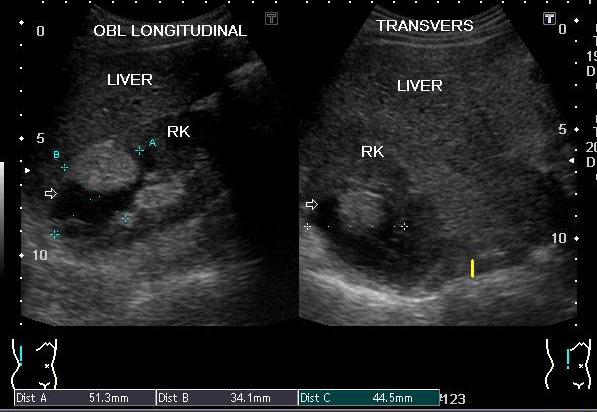

A 58-year-old man presented with history of flank pain. Physical examination showed no palpable masses. Laboratory investigations were in the normal range. Ultrasonography (US) revealed a well circumscribed 4.8 x3.6 x 3.7 cm mass arising within the upper pole of the right kidney (Figure 1). The mass consisted of predominantly hypoechoic portion which demonstrated posterior acoustic enhancement. There is also a hyperechoic component overlaying the cystic portion with fat fluid level suggesting the diagnosis of dermoid cyst. Pre and post IV contrast abdominal CT done with 128 slice CT machine reveled 4.8 x 3.8 x 3.7 cm well circumscribed mass in the upper pole of the right kidney (Figure 2). The mass had a fat attenuation component overlaying the predominant fluid attenuation component with clear fat fluid level. No calcification was seen which confirmed the diagnosis.

Figure 1: Ultrasound image depicting cystic mass in the upper pole of the right kidney with hyperechogenic fat overlaying the cystic component.